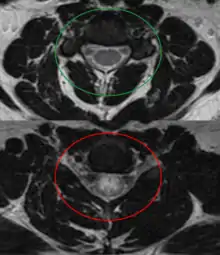

![]() صورة بالرنين المغناطيسي توضح آفة بسبب التهاب النخاع المستعرض (الآفة هي اللون الأفتح، شكلها بيضوي في المركز باتجاه اليمين)، أخذت هذه الصورة بعد 3 أشهر من تعافي المريض. صورة بالرنين المغناطيسي توضح آفة بسبب التهاب النخاع المستعرض (الآفة هي اللون الأفتح، شكلها بيضوي في المركز باتجاه اليمين)، أخذت هذه الصورة بعد 3 أشهر من تعافي المريض. | |